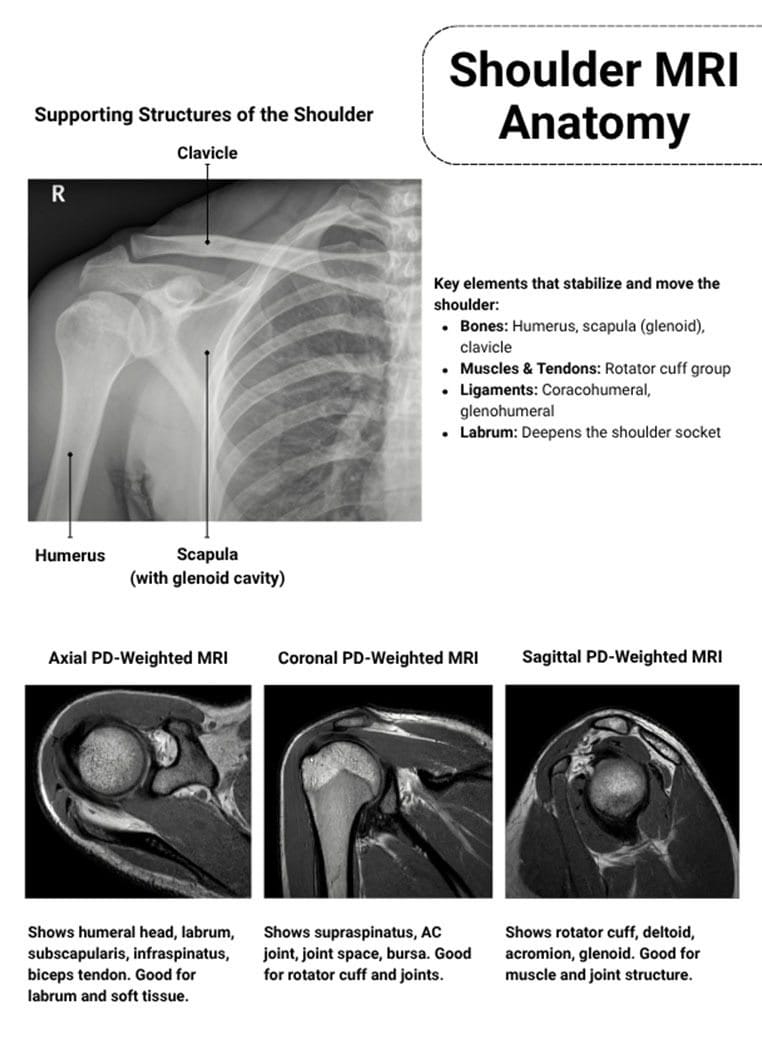

Shoulder pain is one of the most common musculoskeletal complaints (Ashir et al., 2020). While radiographs offer a crucial preliminary examination and ultrasound can help identify full-thickness tears for shoulder evaluation, magnetic resonance imaging (MRI) offers superior, all-encompassing imaging of soft-tissue components, particularly the rotator cuff, and labrum, making it the preferred technique for pain management technicians (Imaging, 2018). The non-ionizing radiation, excellent resolution, and multiplanar imaging of magnetic resonance imaging (MRI) make it an essential diagnostic tool for the assessment of the ligamentous structures, joint capsule, and cartilage. It is important to discuss how Manhattan MRI helps cater to this problem and provides lifelong solutions to patients who suffer from localized or diffused shoulder-related pain.

When assessing shoulder pain and clinical impingement syndrome, magnetic resonance imaging (MRI) is commonly regarded as the preferred imaging modality. This is due to its capacity to show the link between the coracoacromial arch’s overlying osseous and soft tissue components, as well as its direct evaluation of all the soft tissue structures of the subacromial area (Fritts & Craig, 1994). Medical practitioners commonly prefer MRIs for shoulder pain because of their ability to provide enhanced soft tissue imaging, rotator cuff assessment, evaluation of bony structures, assessment of joint inflammation, preoperative planning, and guidance for minimally invasive interventions.